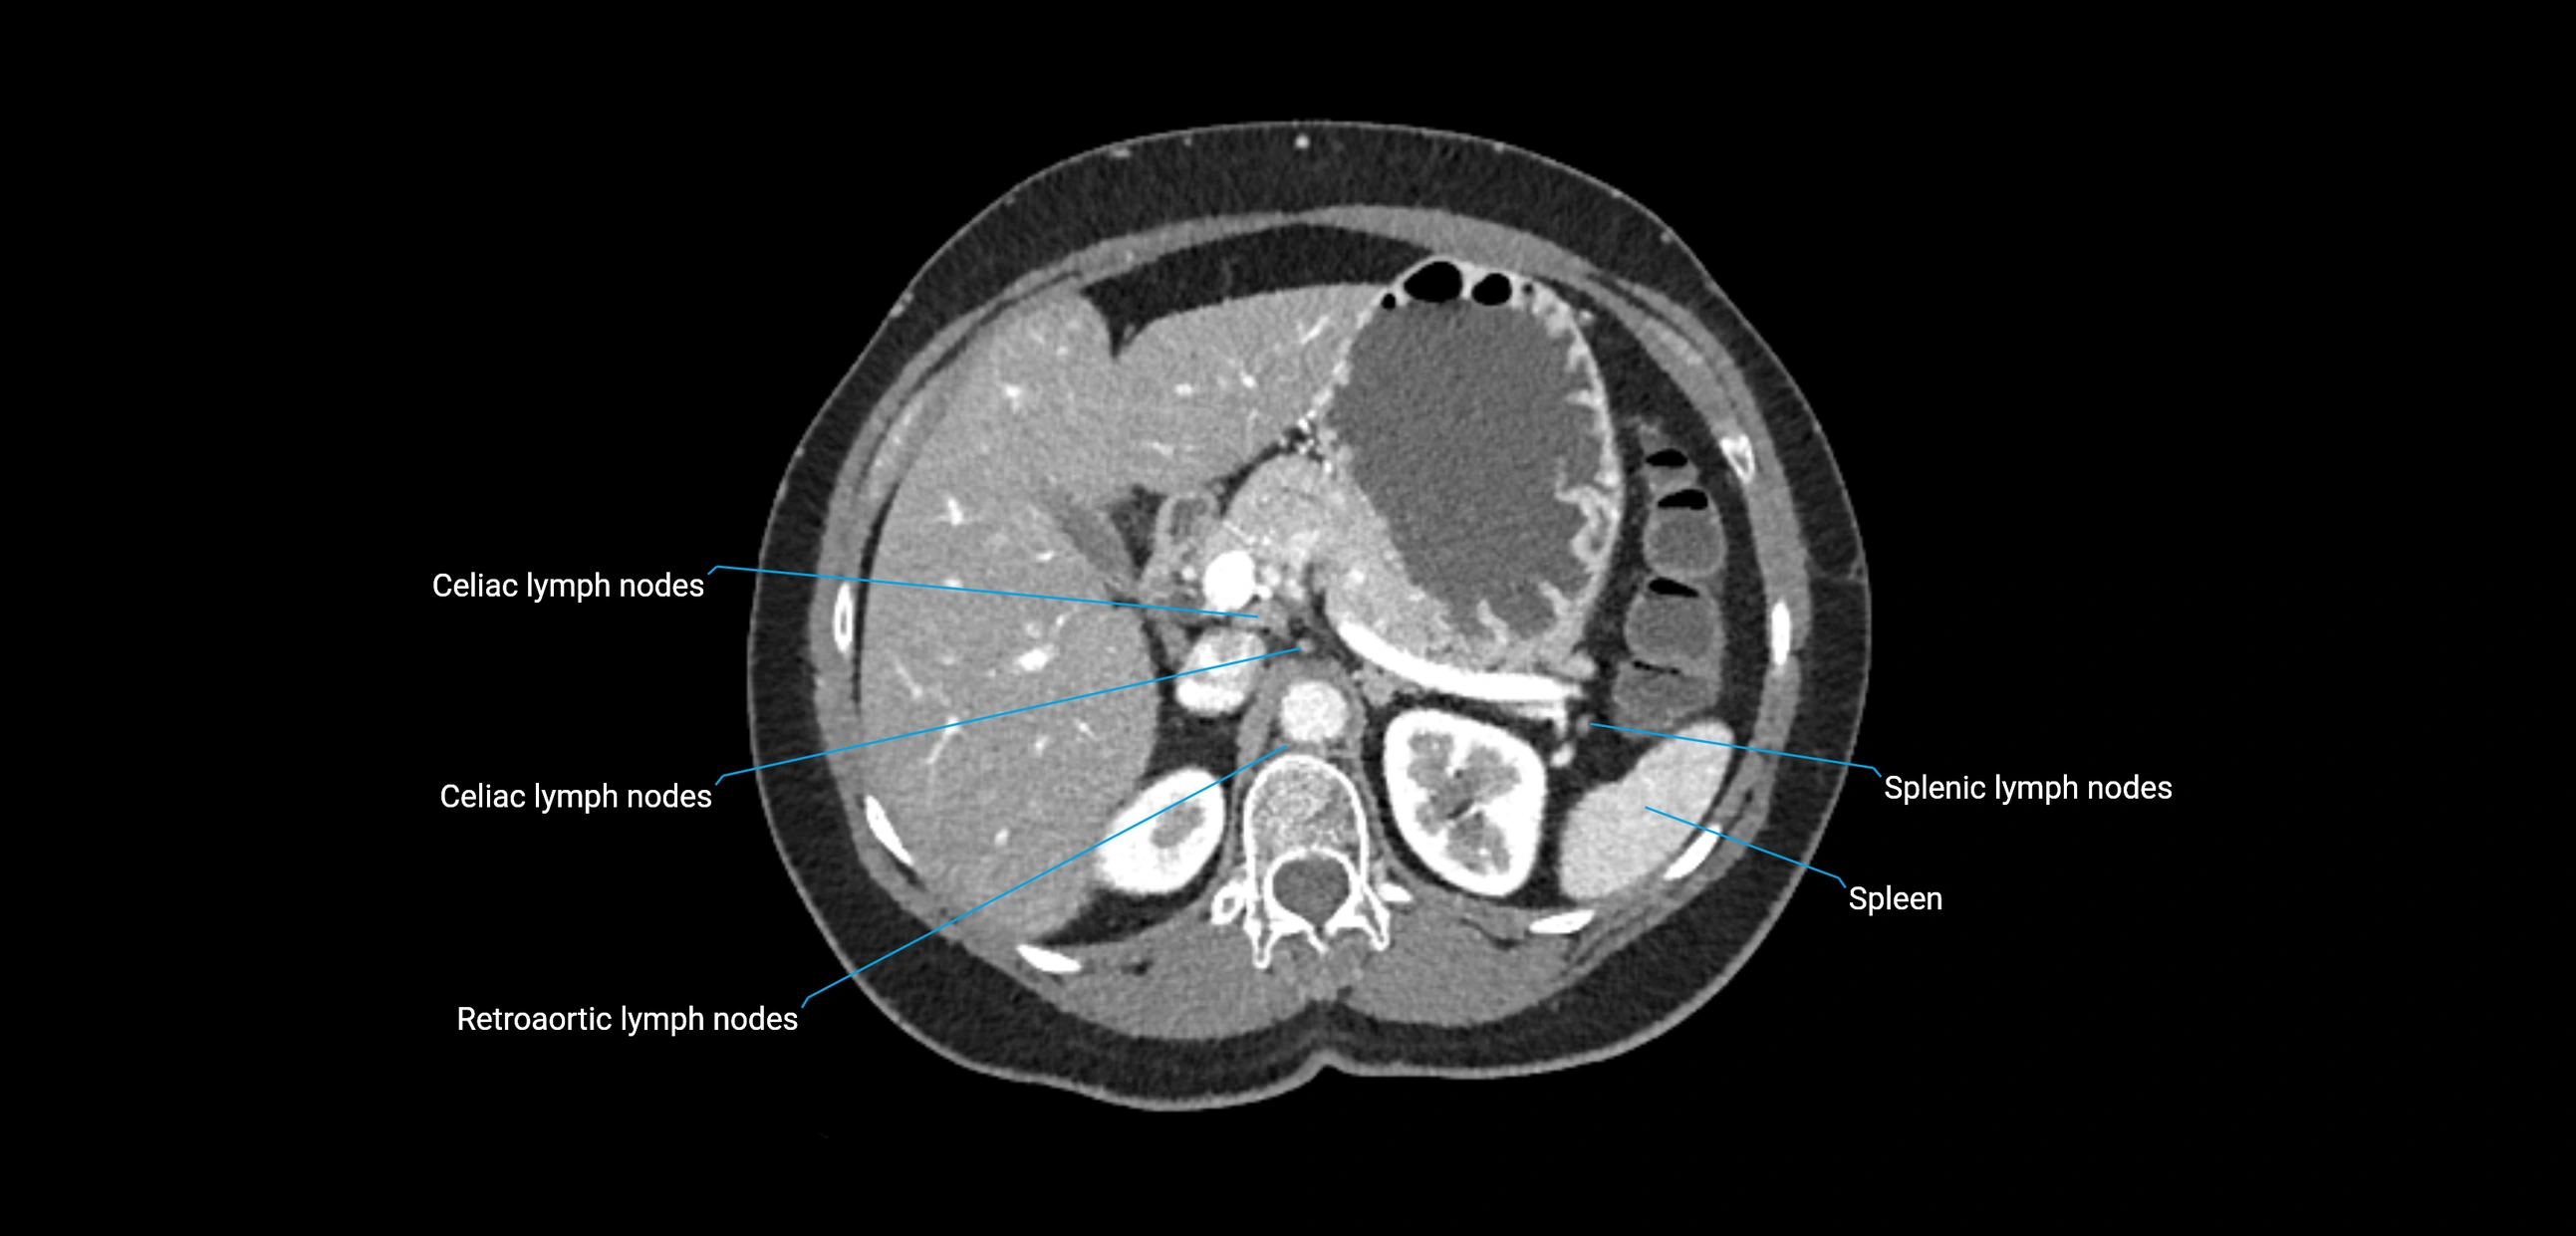

CT Appearance

CT Pre-Contrast:

• Nodes appear as soft-tissue density nodules adjacent to the aorta and IVC

• Calcification may be seen in chronic infections (e.g., tuberculosis)

CT Post-Contrast:

• Normal nodes enhance homogeneously

• Malignant nodes may show heterogeneous enhancement, central necrosis, or conglomerate formation

• Size >1 cm short axis is suspicious, though morphology and distribution are equally important